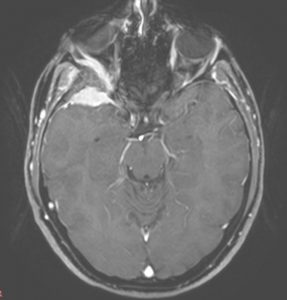

Ασθενής γυναίκα, 41 ετών με εξόφθαλμο δεξιά.

H Μαγνητική & Αξονική Τομογραφία εγκεφάλου ανέδειξε χωροκατακτητική εξεργασία στην περιοχή της πτέρυγας του σφηνοειδούς οστού, δηλ. του άνω (οροφή) και του πλαγίου τοιχώματος του οφθαλμικού κόγχου. Η εξεργασία επεκτείνονταν κατά μήκος της σκληράς μήνιγγας ενώ στην περιοχή του κροταφικού πόλου παρουσίασε ενδοκρανιακή επέκταση. Η πάχυνση του οστού του κόγχου προκαλούσε πίεση των περιεχομένων του κόγχου με αποτέλεσμα εξόφθαλμο.